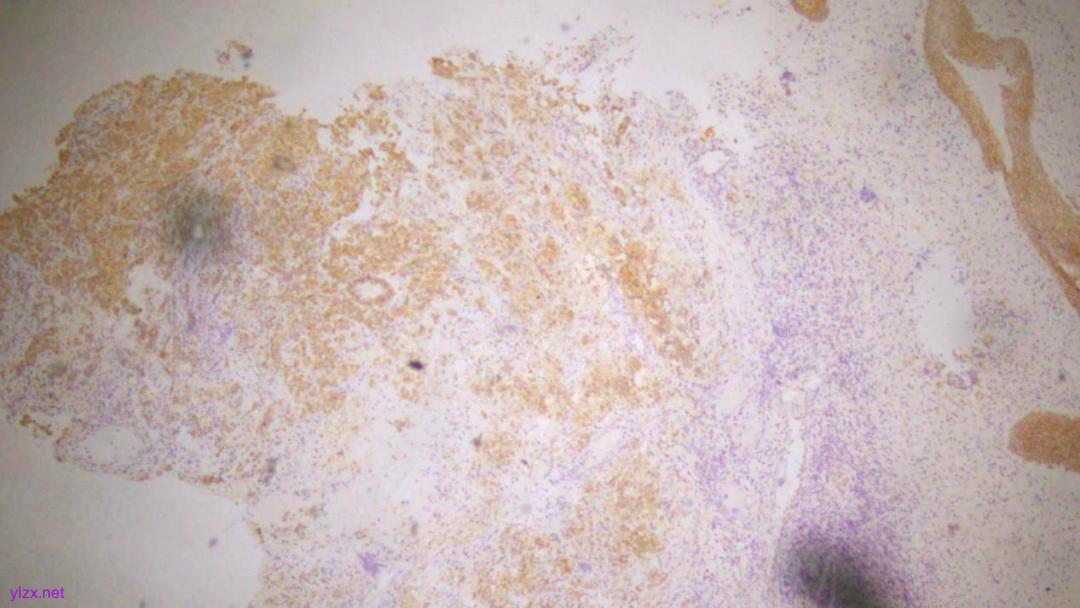

IHC结果:

P120(浆+),P16(灶+),P53(野生型表达),Her2(1+),CK7、GATA3、GCDFP-15、CK-H均(+),ER、PR、E-Cadherin、CK20均(-),Ki67(约5%+)

ER(-)

PR(-)

P120(+)

P120(部分+)

E-Cadherin(-)

GCDFP-15(弥漫+)

GATA-3(+)

CK7(弥漫强+)

Her2(1+)

Ki-67(散在+)

(宫颈2点、5点、10点活检组织及宫颈管搔刮组织)HE形态结合临床病史、免疫组化结果,符合乳腺浸润性小叶癌转移。